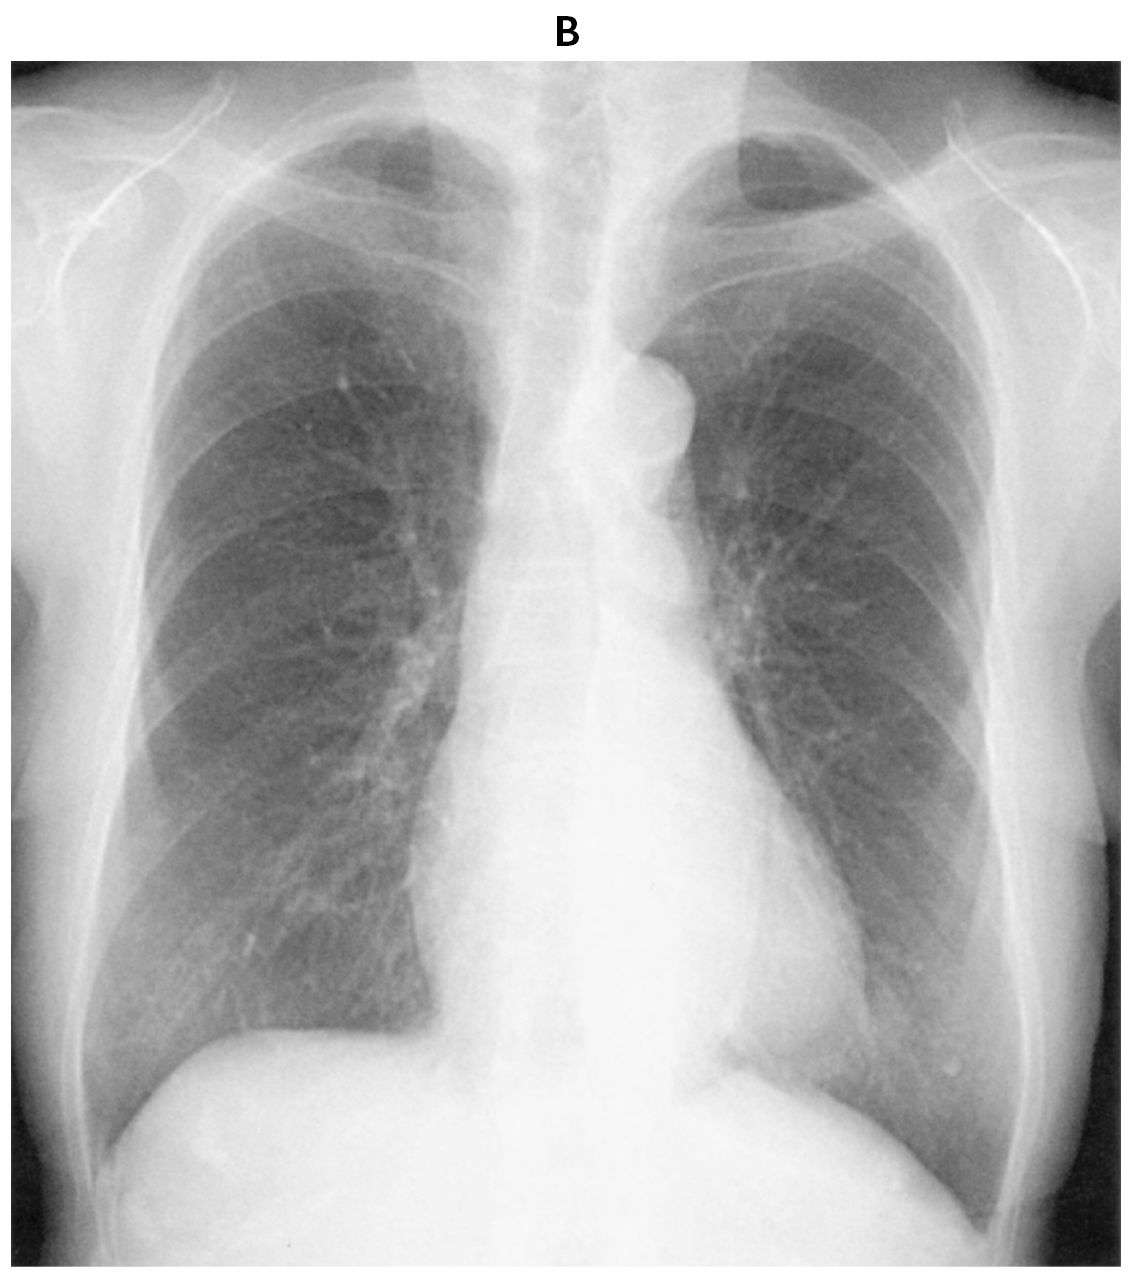

78歳の女性。動悸を主訴に来院した。高血圧で治療中である。1か月前から週に1回程度,誘引なく動悸症状があるが数分で改善していた。3日前から動悸症状が持続している。日常生活には支障はないが,症状が持続するため受診した。意識は清明。身長156cm,体重45kg。脈拍116/分,不整。血圧108/68mmHg。SpO2 98%(room air)。心音と呼吸音とに異常を認めない。心エコー検査では左室壁運動は良好に保たれている。12誘導心電図(A)と胸部エックス線写真(B)とを下に示す。

無料会員登録していただくと、実際の解説をすべて見ることができます。急性の呼吸困難を主訴とする疾患としては,喉頭浮腫,気道異物,自然気胸,気管支喘息,慢性閉塞性肺疾患の急性増悪などの呼吸器疾患,心不全(急性,慢性の急性増悪),肺血栓塞栓症などの循環器疾患が代表的である。この症例では呼吸器感染症と心不全が疑われるが,胸部エックス線写真は肺炎像というよりも両心不全を示唆する所見を示している。診断:心不全(両心不全)(Nohria分類wet and warm) 選択肢考察 ×a 強い呼吸困難,胸痛などにより安静が保てない場合には,血管拡張による前負荷軽減と,交感神経抑制による心筋酸素消費量の減少を目的としてモルヒネを使用する。この症例ではモルヒネが必要となるほどの興奮状態ではない。